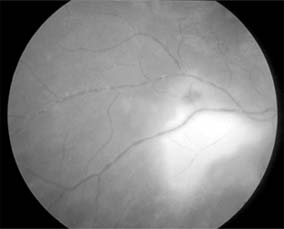

Figure 15-25

Figure 15-25: Sarcoidosis. Focal periphlebitis and disk leakage may respond dramatically to systemic corticosteroids. Left: Before treatment. Right: After 6 weeks of treatment with prednisolone, 30 mg daily.

Figure 15-26

Figure 15-26: Sarcoidosis. Retinal pigment epithelial and choroidal disease may be very distinctive (left) and highlighted by fluorescein angiography (right).